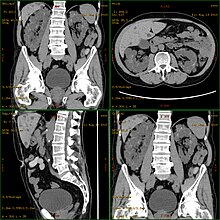

![]() | |

| Severely affected polycystic kidneys removed at time of transplantation | |

Polycystic kidney disease can be ascertained via a CT scan of abdomen, as well as, an MRI and ultrasound of the same area. A physical exam/test can reveal enlarged liver, heart murmurs and elevated blood pressure[1]